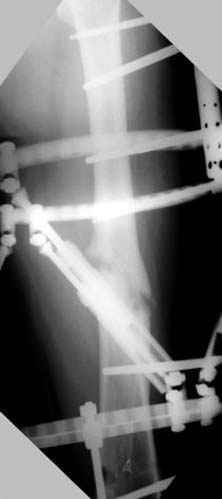

7:30 начало операции, больной на спине, попытка репозиции после анестезии N3, укладка больного на боку, доступ Kocher- Langenbeck, состояние седалищнего нерва около 2.5см кровоподтек, через joistick головка бедра приподнята, освобовождение сустава, фрагмент заднего края более 3х4 см репонирован на свое место. После промывания

сустава, репозиция вывиха (N4), фиксация фрагмента 2.7(4) мм шурупами и допольнительно реконструктивной пластиной на 8 дырок, фиксация 3.5мм шурупами проксимально и дистально.

Интраоперционные N5 косая запирательная и N6 подвздошный снимок

11:50 больной в послеоперационной, рентгенограмма N7, компьютерная томограмма в тот же день N8-10